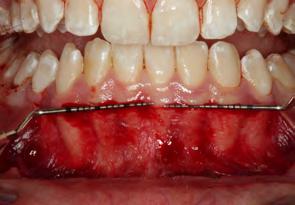

Figura 1. Fotografia inicial, se observa un fenotipo delgado festoneado, estrecha banda de encía queratinizada en zona anteroinferior con sobremordida, apiñamiento y retroinclinación en el maxilar anterior inferior.

Paciente femenino de 13 años de edad, acude con sus padres a la clíni ca de periodoncia de la Universidad Popular Autónoma del Estado de Puebla para revisión dental. Al reali zar la exploración clínica, en su aná lisis gingival, la paciente presenta un fenotipo gingival delgado, con estre cha banda de encía queratinizada en el maxilar anteroinferior, edema y eri tema en zona marginal y papilar, acu mulación de biofilm dental en zonas interproximales y marginales, retroin clinación y apiñamiento anteroinfe rior, con una notoria sobremordida y paladar profundo. Posteriormente al realizar periodontograma y aná lisis radiográfico se diagnostica a la paciente con una gingivitis inducida por biofilm dental y según la nueva clasificación del World Workshop del 2017 presenta deformidad mucogin gival alrededor de los dientes por la estrecha banda de encía queratiniza da (Figura 1).